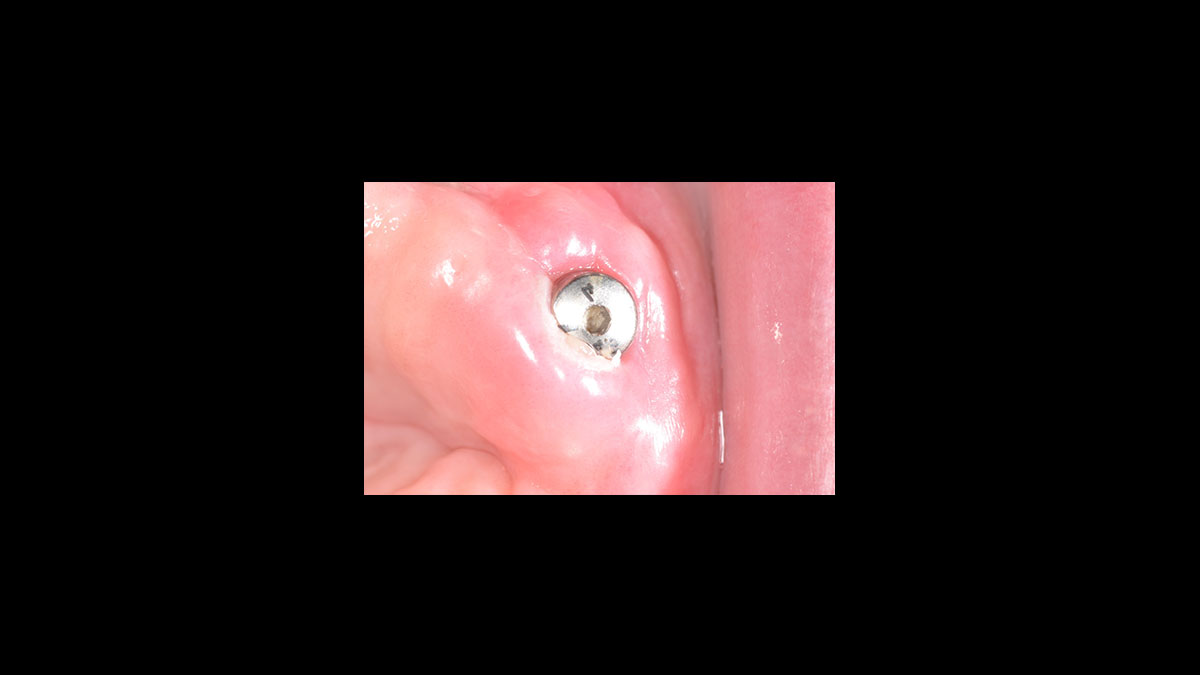

Descubrimiento del implante

• Descubrimiento del implante